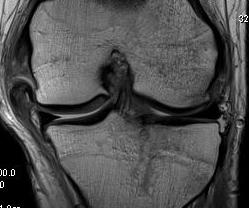

MRI

Classification

Grade I: intact ligament with periligamentous oedema

Grade II: partial tearing with surrounding oedema

Grade III: complete ligament tear

Sites

Femoral avulsion

Midsubstance

Tibial side: wave sign, ensure that the MCL is no flipped above pes anserinus as will not heal (analogous to Stener lesion)

Acute femoral avulsion

Midsubstance MCL tears

Wave sign indicative of tibial avulsion, with ligament retracted above pes anserinus / hamstring tendons

In the chronic setting see thickening of the MCL